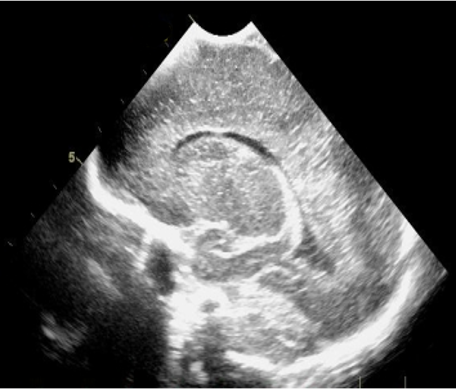

Neonatology Grade 1 PVL 1 Image